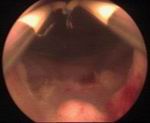

Prostatic enlargement is a comman problem is old age. By TURP nearly all patient who requires surgery for prostate can be treated successfully without any incision. Under anesthesia per urethral scope is inserted & under vision prostate is resected. Patient requires 2 to 4 days hospitalization & 1 week rest. Usually patient does not requires blood transfusion & patient can tolerate endoscopic surgery very well without risk of incontinance of urine.